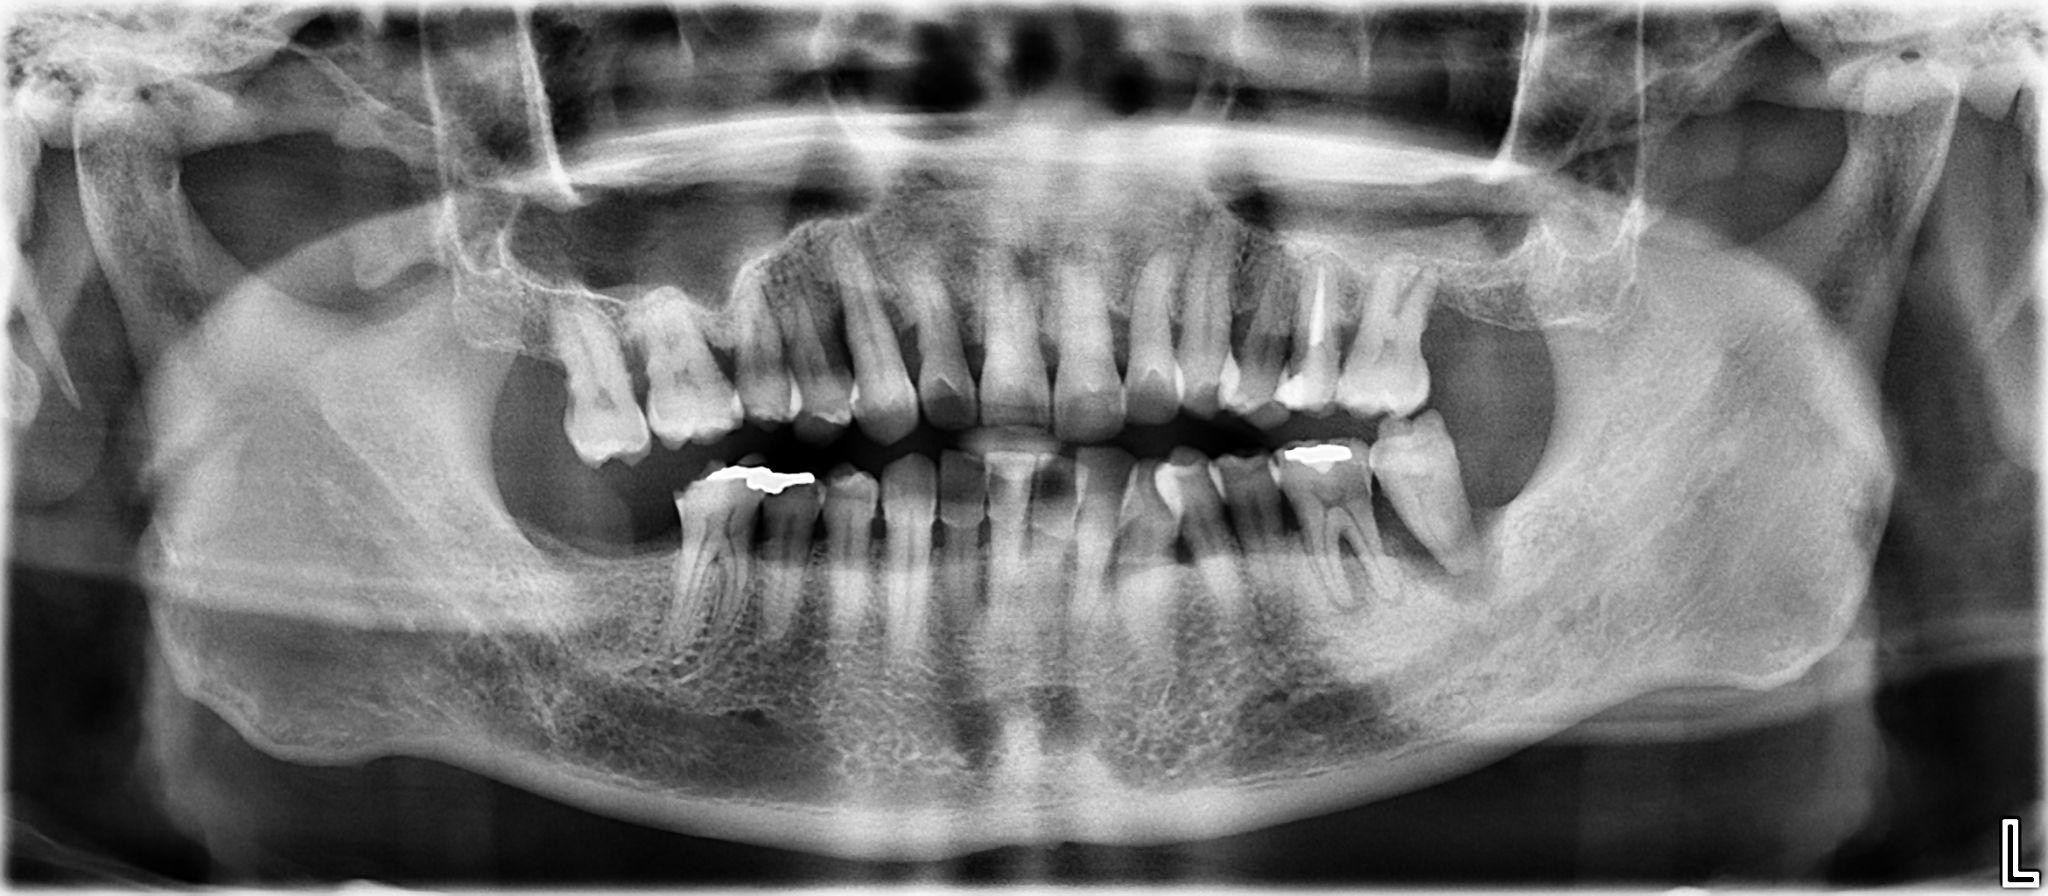

17. What options can be selected for the first quadrant of this panoramic X ray?

18 / 24

18. What options can be selected for the second quadrant of this panoramic X ray?

19 / 24

19. What options can be selected for the third quadrant of this panoramic X ray?

20 / 24

20. What options cannot be selected for the forth quadrant of this panoramic X ray?

21 / 24

21. What options can be selected for the first quadrant of this panoramic X ray?

22 / 24

22. What options cannot be selected for the second quadrant of this panoramic X ray?

23 / 24

23. What options can be selected for the third quadrant of this panoramic X ray?

24 / 24

24. What options can be selected for the forth quadrant of this panoramic X ray?